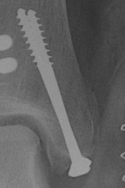

Fixation options

| Screw fixation | Tension band wire | Buttress plate |

|---|---|---|

| Type C: transverse fractures |

Type B: too small for two screws |

Type D: Vertical fractures |

Screw fixation

AO surgery reference medial malleolus lag screws